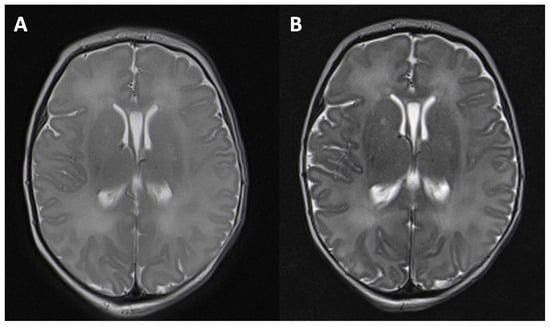

| 10–18 | 34 | −0.10 | −0.04 | 0.03 | 0.05 | <0.001 (*) |